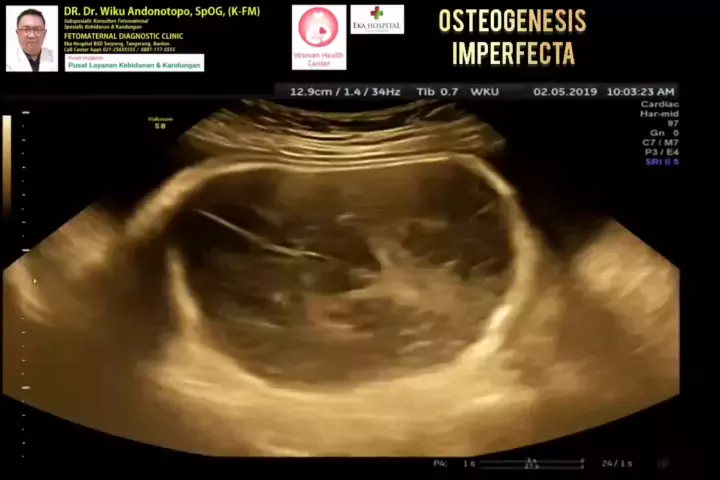

Osteogenesis Imperfecta... #osteogenesisperfecta #osteogenesisinperfecta #usgfetomaternalekahospitalbsd #usgfetomaternalbsd #fetomaternalekahospitalbsd #ekahospitalbsd #drwikuandonotopo #polikandunganekahospitalbsd # # #fouyoupage